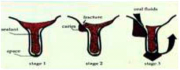

| 09:10, 18 ביוני 2013 | איטומי חריצים5.png (קובץ) |  |

77 קילו־בייטים | Motyk | 1 | |

| 09:07, 18 ביוני 2013 | איטומי חריצים4א.png (קובץ) |  |

159 קילו־בייטים | Motyk | 1 | |